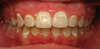

Dans le cas d’un brossage insuffisant, sur une période plus longue, un dépôt de plaque dentaire autour des bagues et à la limite de la gencive peut entraîner un début de déminéralisation de l’émail se traduisant par une marque blanchâtre. Dans un premier temps cette marque est réversible à l’aide de traitements fluorés, mais irréversible à un stade plus avancé. Le stade suivant étant une carie.

Exemple de taches apparaissant avec un mauvais brossage